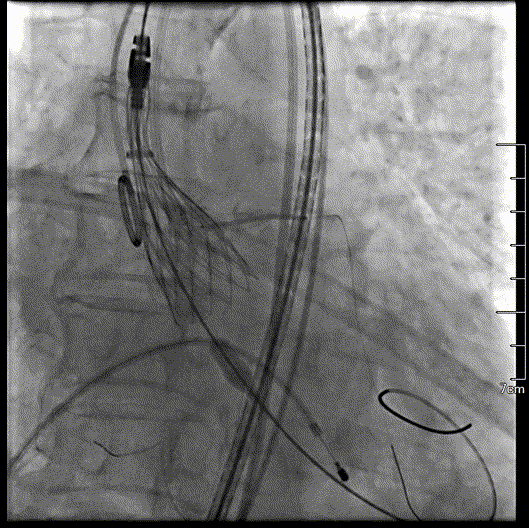

瓣膜完全释放过程